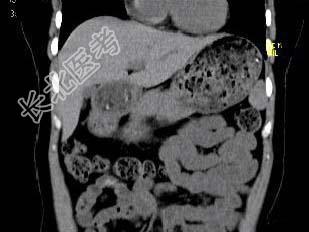

- 单项选择题根据所提供的图像,最可能的诊断是 ( )

A、正常肝血管

B、肝内胆管扩张

C、布-加综合征

D、肝血管瘤

E、以上都不是